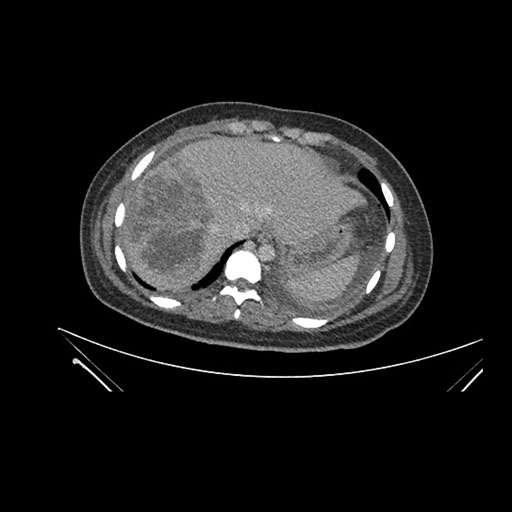

Imaging Analysis

Look through the patient's CT scan to identify any areas of concern for the necessary procedure.

Based on initial findings, which issue(s) would you be most concerned about?